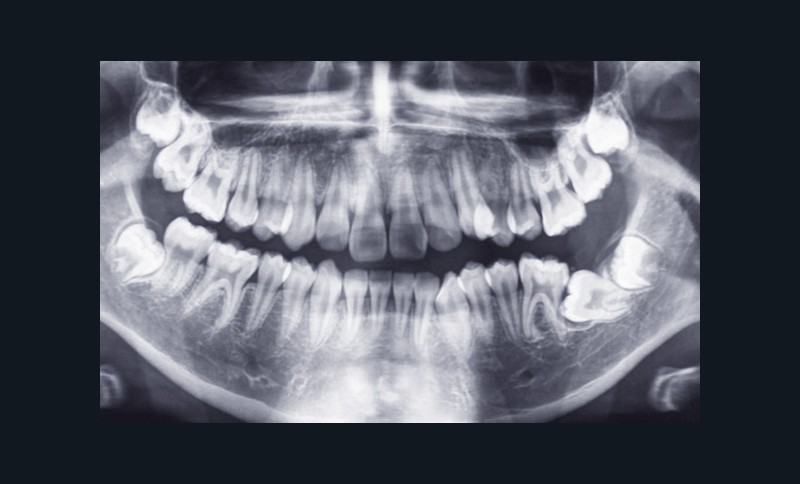

Charlotte présente donc une absence de 11, un surplomb et un recouvrement augmentés associés à une retromandibulie. La patiente a un profil convexe, hypodivergent avec une proalvéolie maxillaire et une classe II d’Angle. (fig. 1a à h). La radiographie panoramique confirme l’absence de 11 et la téléradiographique de profil, révèle une classe II squelettique (ANB : 6°, AoBo : 9 mm) par rétromandibulie ainsi qu’une proalvéolie maxillaire prononcée.

(I/Na : 40° I-Na : 7 mm) (fig. 2a et b).